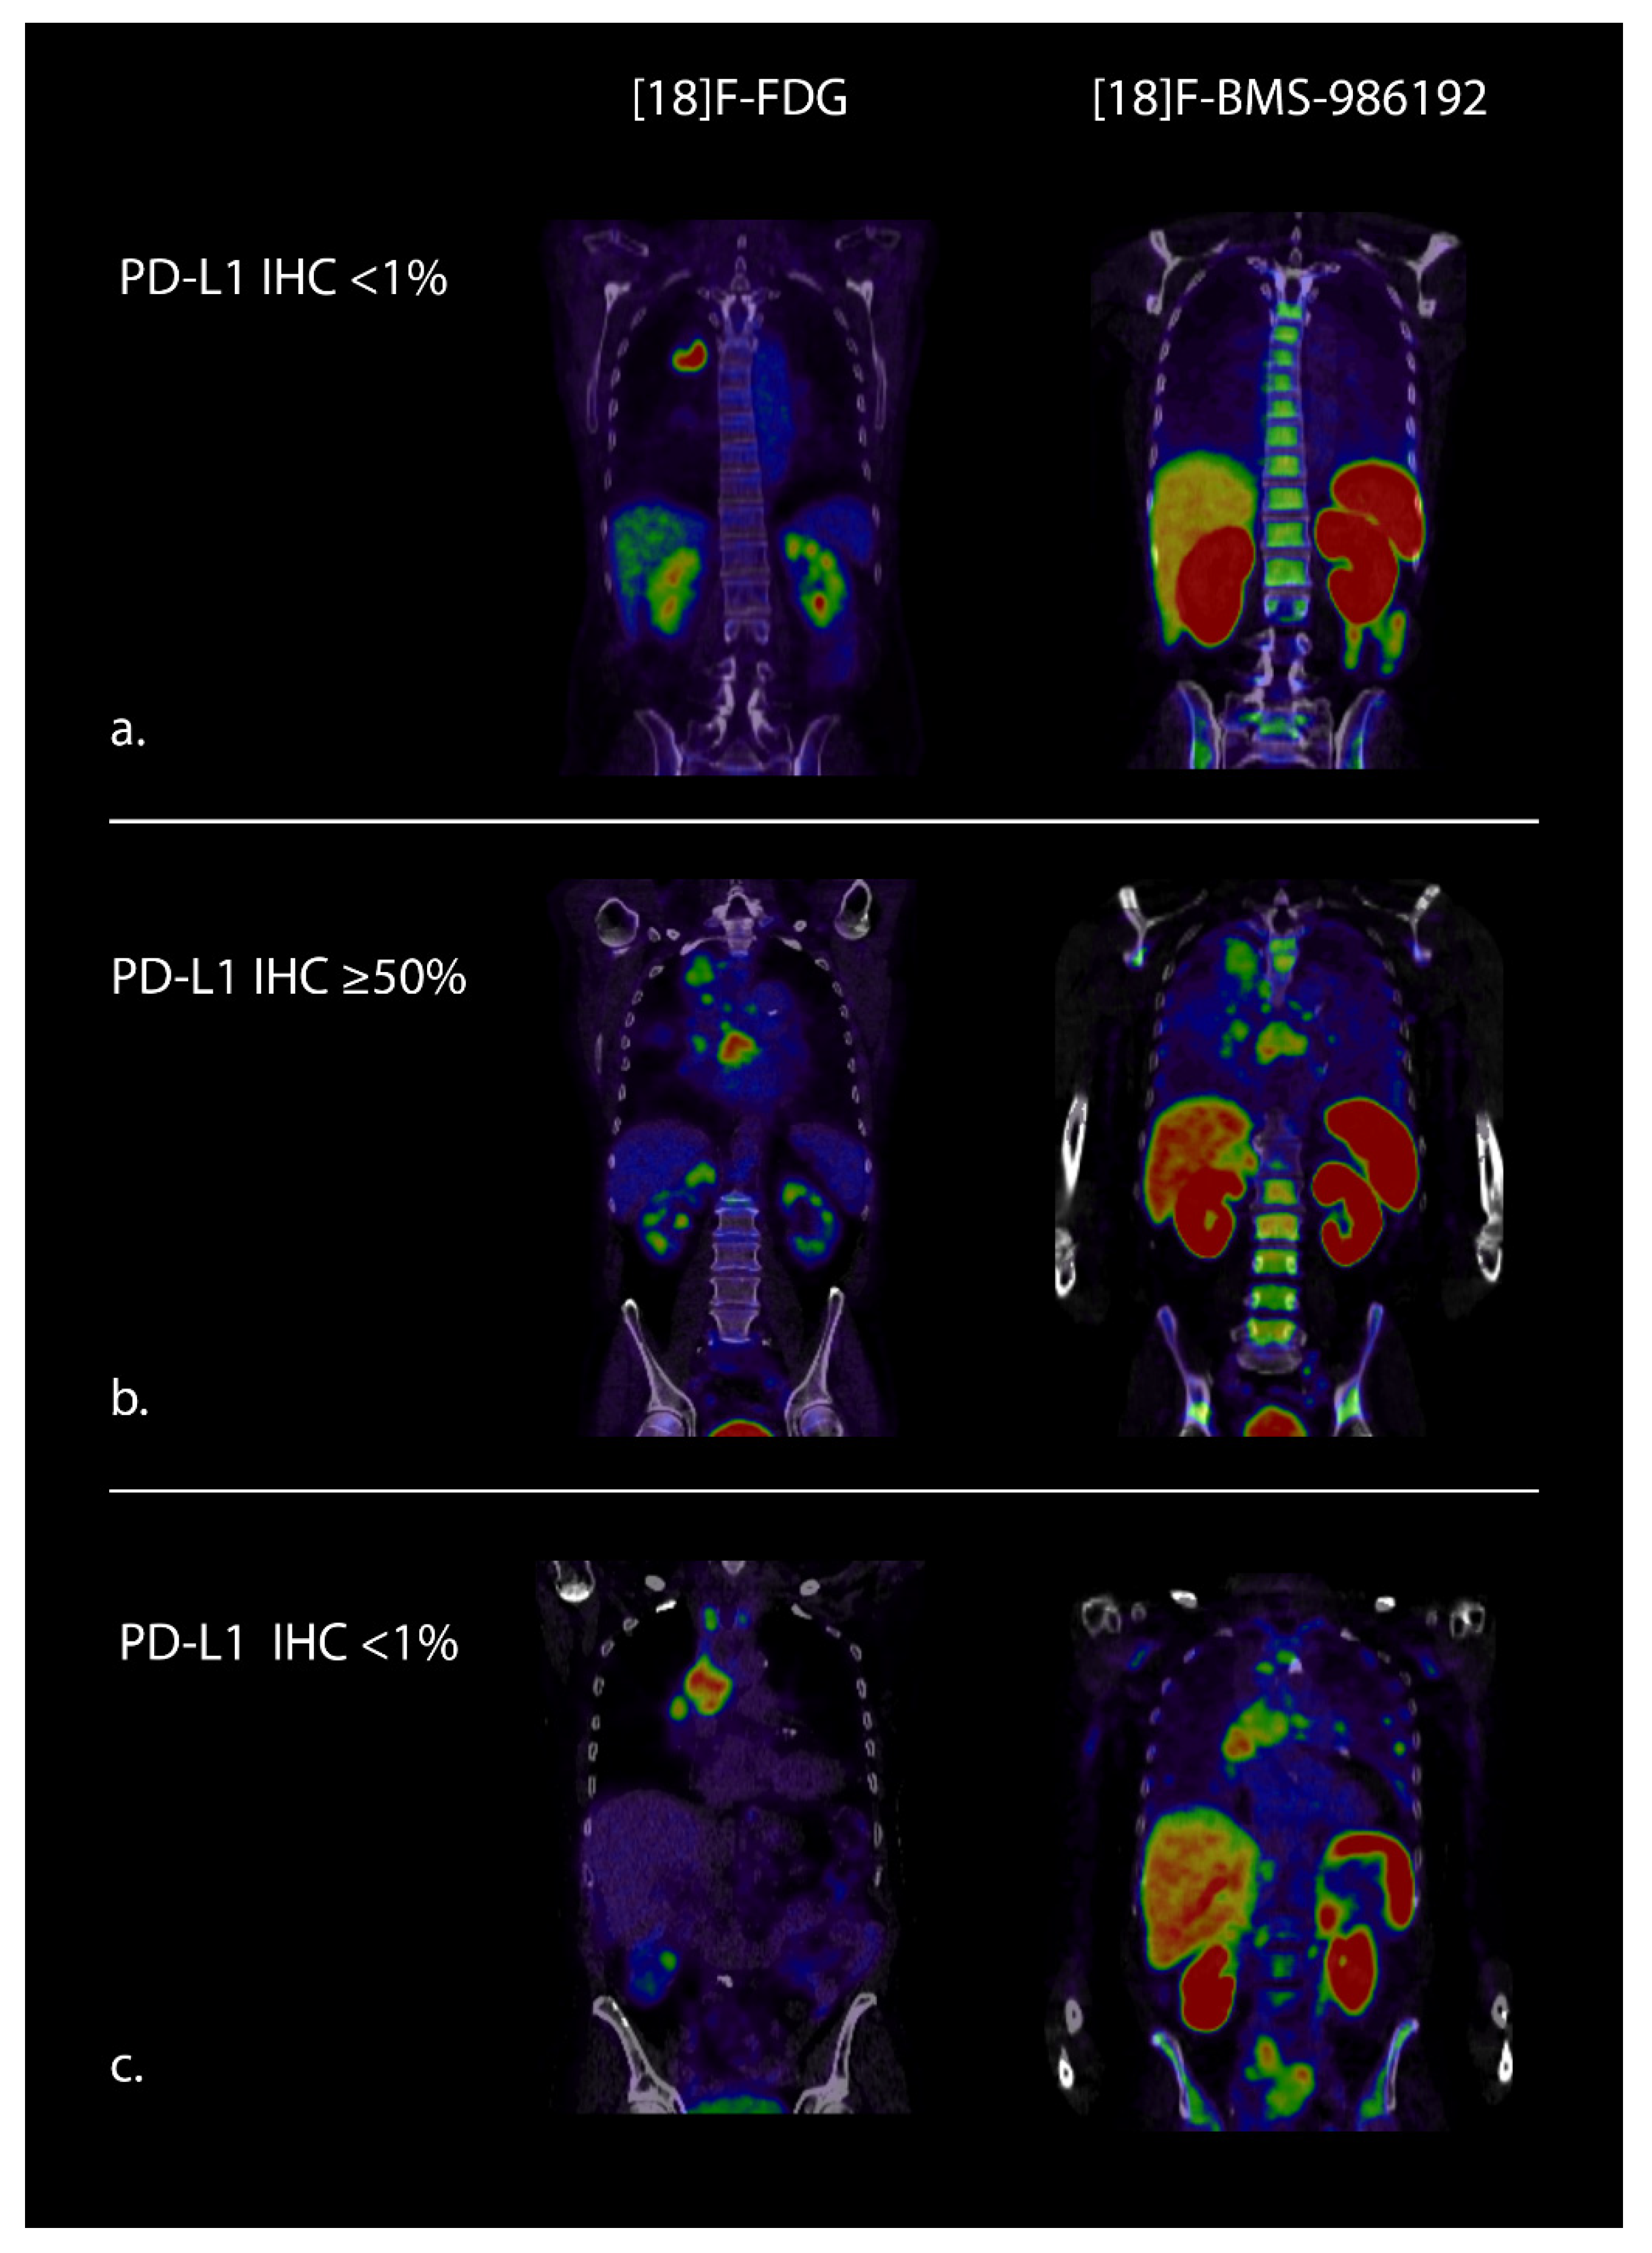

- Niemeijer, A.N.; Leung, D.; Huisman, M.C.; Bahce, I.; Hoekstra, O.S.; Van Dongen, G.A.M.S.; Boellaard, R.; Du, S.; Hayes, W.; Smith, R.; et al. Whole body PD-1 and PD-L1 positron emission tomography in patients with non-small-cell lung cancer. Nat. Commun. 2018, 9, 1–5. [Google Scholar] [CrossRef]

- Stutvoet, T.S.; van der Veen, E.L.; Kol, A.; Antunes, I.F.; de Vries, E.F.; Hospers, G.A.; de Vries, E.G.E.; de Jong, S.; Lub-de Hooge, M.N. Molecular imaging of Pd-L1 expression and dynamics with the adnectin-based pet tracer (18)F-Bms-986192. J. Nucl Med. 2020, 61, 1839–1844. [Google Scholar] [CrossRef]